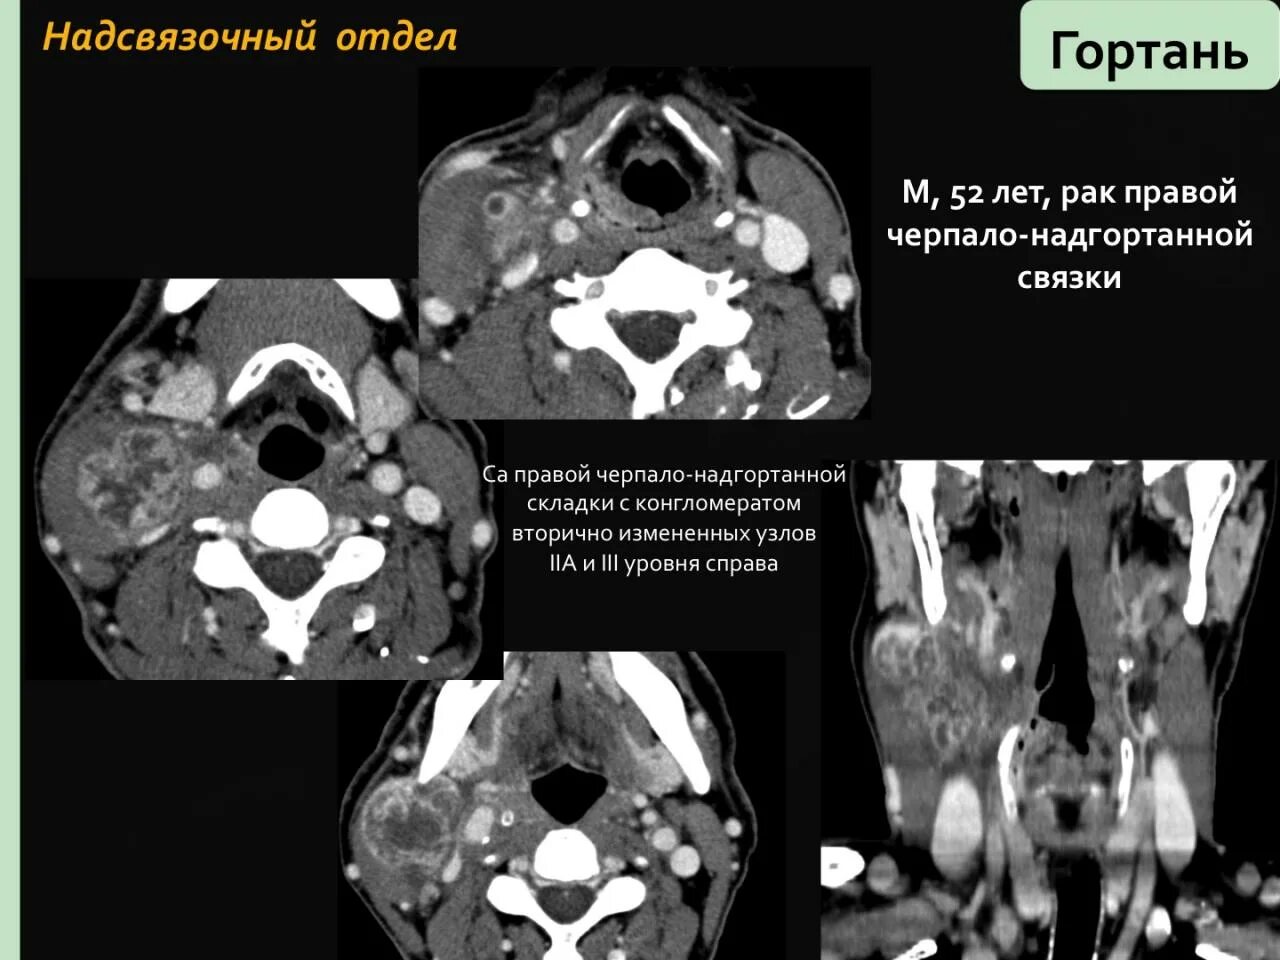

Как на кт выглядит рак